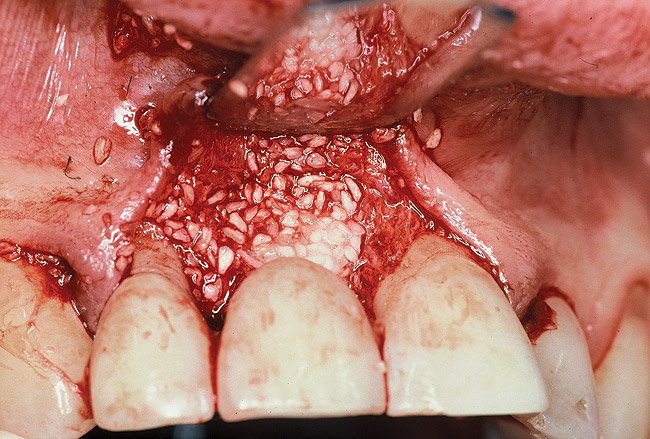

Figure 8  Flap reflection revealed circumferential bone loss.

Figure 8

Figure 9: Following implant surface decontamination and enamel matrix derivative applications, the defect was filled with a mineralized allograft combined with a biologic.

Figure 9